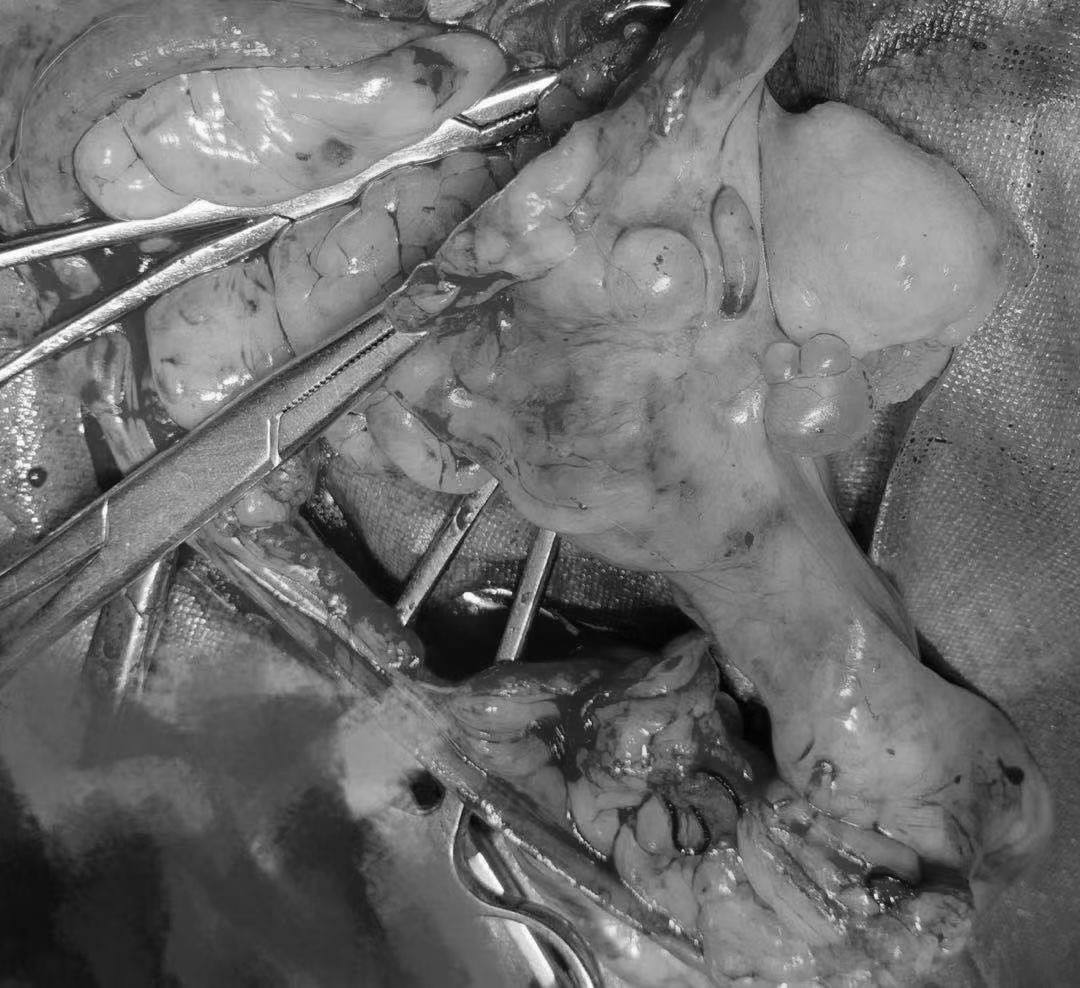

10岁的德牧,乳腺肿瘤切除

未做绝育,子宫同时出现病变